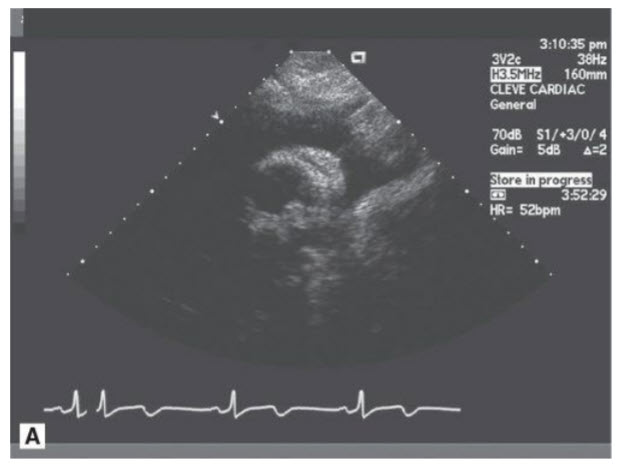

A 37-year-old patient presents with fever, weight loss, and blood cultures that are positive for Pseudomonas and the transthoracic echo finding in Figure below.

The patient’s most likely demographic for this clinical scenario is:

Intravenous (IV) drug abuser. Right-sided endocarditis is less common than left-sided endocarditis. The TEE image (Fig. below) shown demonstrates a patient with a vegetation on the tricuspid valve, and the organism identified by culture is Pseudomonas. This is associated with IV drug use with contamination at the time of injection. Although the other clinical situations listed are at increased risk for endocarditis (typically left sided), Pseudomonas would be a very unusual pathogen in those situations.